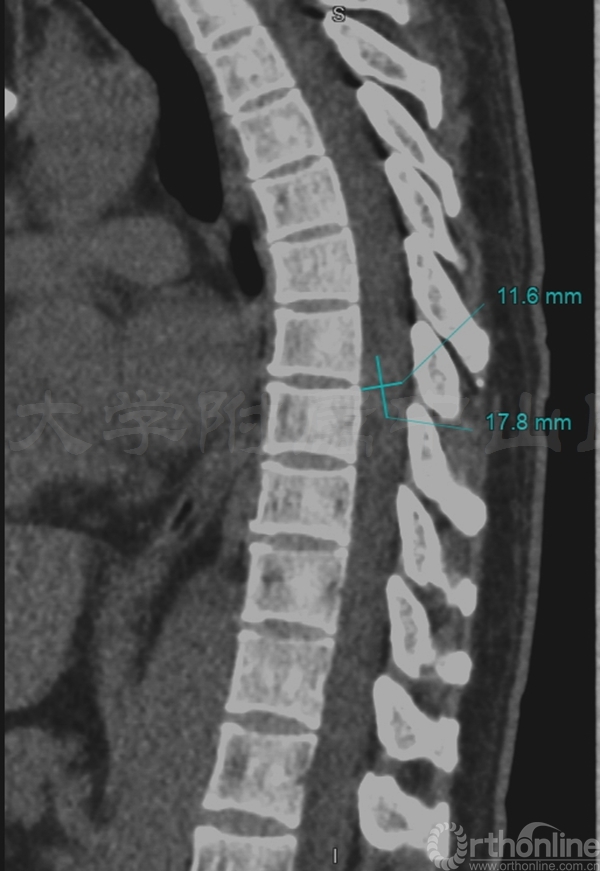

术前三维CT:T7/8水平可见椎管内占位

术前MRI:T7-8水平椎管内占位伴脊髓变性,脊膜瘤可能的大